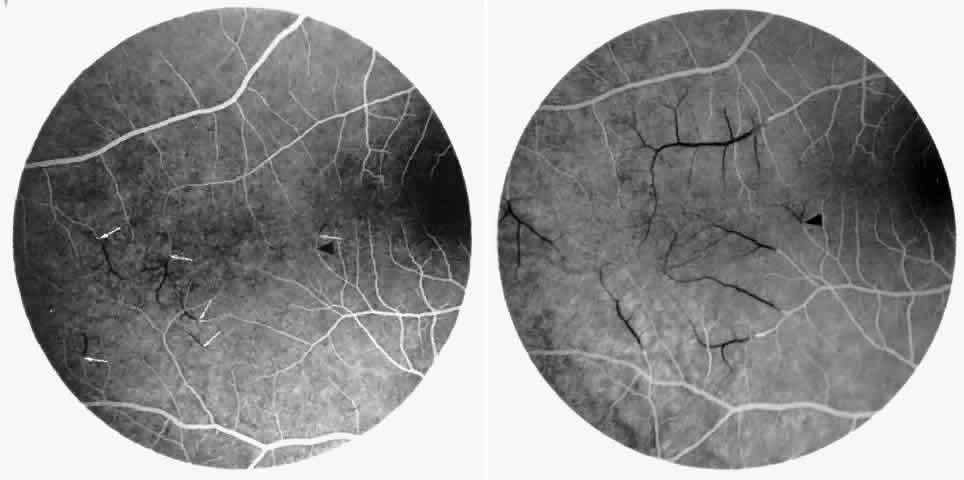

Other macular and perimacular changes include microaneurysm-like dots, dark and enlarged segments of arterioles, hairpin-shaped venular loops, pathologic avascular zones, and widening and irregularities of the foveal avascular zone (Figs. 11 and 12). In the Jamaican cohort study evaluating children with homozygous sickle cell anemia and SC disease between the ages of 5.0 and 7.5 years of age, no pathologic avascular zones could be identified despite a high incidence of peripheral vascular closure.31 In evaluating patients with homozygous sickle cell anemia, no relationship between ISC counts and macular abnormalities or visual acuity could be found.101 Using fluorescein angiography, investigators have found the foveal avascular zone to be significantly larger in eyes with clinical evidence of sickle cell maculopathy as compared with normal eyes and eyes without clinical evidence of sickle cell maculopathy.102–104

Fig. 11. A. A 40-year-old woman with homozygous sickle cell anemia. A fluorescein angiogram demonstrates multiple microaneurysm-like dots with fluorescein leakage, hairpin loop (arrowhead), pathologic avascular zones (arrows), and a widened, irregular foveal avascular zone (FAZ). B. Fluorescein angiogram of a 30-year-old woman with homozygous sickle cell anemia demonstrates multiple microaneurysm-like dots and a widened, irregular FAZ.

Fig. 12. A. Fluorescein angiogram of the left eye of a 40-year-old man with homozygous sickle cell anemia, demonstrating an irregular foveal avascular zone (FAZ), hairpin loops, and loss of the temporal capillary network. B. Fluorescein angiogram of the right macula of a 38-year-old woman with homozygous sickle cell anemia, showing an abnormal FAZ, hairpin loop (arrowhead), and pathologic avascular zones (arrows).

Careful examination by fluorescein angiography, looking for areas of capillary dropout and other capillary abnormalities, is often necessary to identify the macular changes. These changes may be transient, and the macula may appear normal on subsequent fluorescein angiograms (Fig. 13). Although fluorescein angiography may or may not demonstrate reperfusion of a previously occluded capillary bed, a loss of the inner retinal layers results in an ophthalmoscopic focal concavity with an abnormal reflex (retinal depression sign) (see Fig. 8E).105,106 These changes are usually permanent. The retinal depression sign is not pathognomonic of sickle cell disease and may be seen with other arteriolar occlusive diseases, such as embolic retinopathy, vasculitis, and hypertension.

Fig. 13. A. A 32-year-old man with homozygous sickle cell anemia and proliferative sickle retinopathy. A fluorescein angiogram shows temporal occlusions and a pathologic avascular zone (PAZ) temporal to the foveal avascular zone. B. Seven years later, there is filling of the previously noted PAZ.